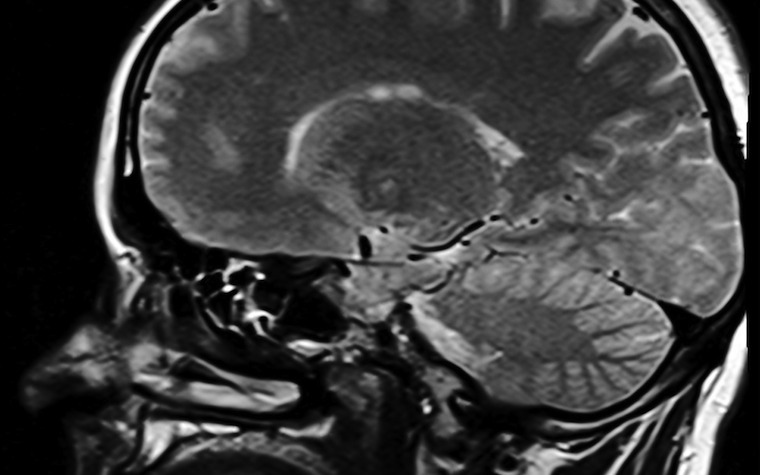

responsible for the fluid swelling that occurs in the brain during mild

traumatic brain injuries, or concussions.

of fluid and swelling of the astrocyte cells. This swelling, or edema, is one